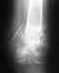

Перелом малой берцовой кости правой ноги.Сделали рентген, один доктор сказал, что закрытый перелом, другой утверждал, что есть небольшое смещение, говорил об операции. В результате сошлись на мнении, что лучше наложить мне лангету и отправили еще в травм пункт. Там посмотрели рентген, тоже по их мнению перелом, но без смещения. Отправили на неделю домой, потом контрольный снимок. Я не знаю, как это у них так расходятся мнения, и может ли быть легковое смещение? Что мне в этом случае делать? Но как мне кажется я сама могу видеть это смещение на снимки, а врачам просто не охота возиться. Подскажите что-нибудь. Ни мог ли кто глянуть на мой снимок? Спасибо